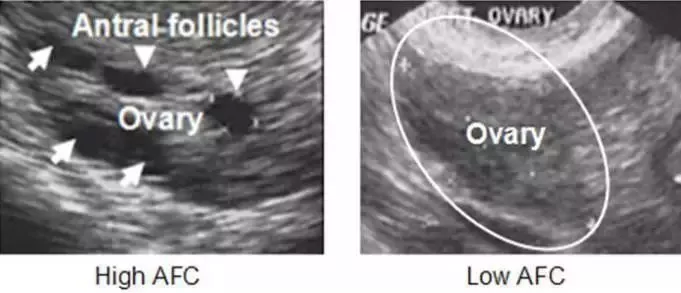

窦卵泡计数(AFC),是在行妇科阴道超声检查的时候,对卵巢中的窦卵泡数量进行计数。通常在月经第2天(也即试管启动时)查验AFC数量作为促排方案制定的重要参考。

通过计数2-9mm大小的窦卵泡数量即可以预测卵巢这两种功能的水平。

其次,AFC可以对试管婴儿治疗中促排卵效果进行预测。窦卵泡数量<5-7个,提示可能获得很少可供使用的卵子;而如果AFC过多,如>20个,则带来促排卵并发症——卵巢过度刺激综合征的风险也大大增加。

第三,有助于一些疾病的诊断。过多的卵泡,如AFC>12个(存在争议,部分认为需要更多),可能提示雄激素水平过高,有助于多囊卵巢综合征的诊断。过少的AFC,如AFC<4个,经常伴随围绝经期的提前。医生通过AFC,增加了诊断准确性,以制定相应的治疗方案。